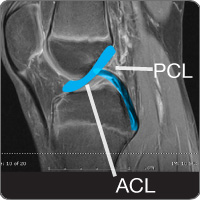

Posterior cruciate ligament injury

cond-pclThe knee contains the posterior cruciate ligament (PCL), which is one of four ligaments (tough bands of tissue) that connect the femur (thigh) bone to the tibia (shin) bone. In combination with the anterior cruciate (ACL), the PCL makes a diagonal "X" through the center of the knee joint and allows the knee to twist/rotate and move side-to-side. The PCL becomes injured or torn when it is stretched beyond its normal range of movement. Research shows that up to 60 percent of PCL injuries may also involve other structures in the knee (meniscus, the pad/disc between the knee bones, cartilage or other ligaments) creating increased instability.